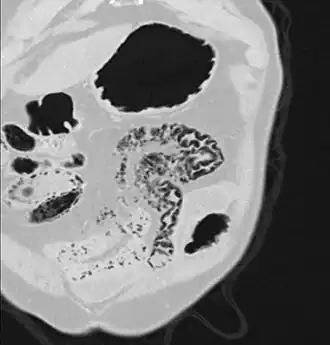

Pneumatosis intestinalis at computed tomography in intestinal ischemia. Lung window for better representation of the gas deposits in the intestinal walls. Coronal reconstruction. -

Pneumatosis intestinalis in computed tomography with intestinal ischemia. Lung window for better representation of the gas deposits in the intestinal walls. -